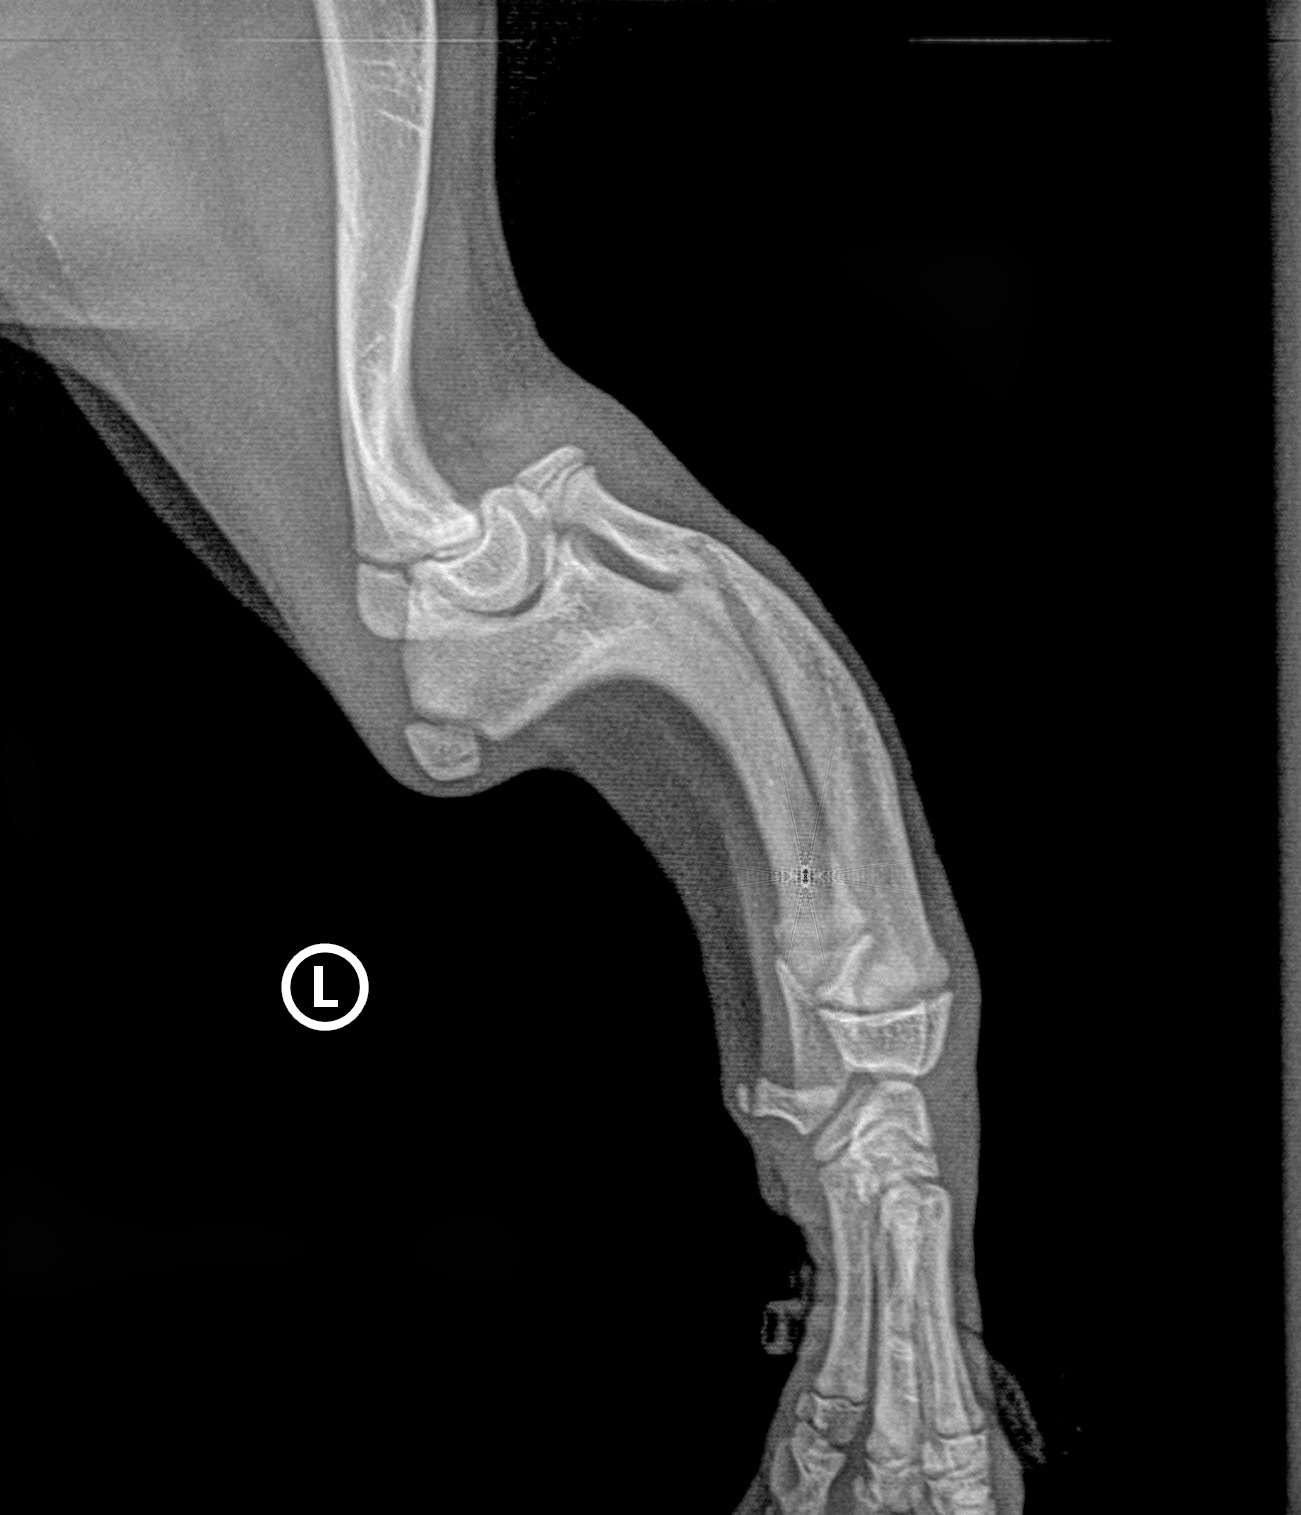

Freddie stammt aus Kroatien und wurde zusammen mit seinen Geschwistern in einem Farbeimer gefunden - wurde also einfach so "entsorgt". Bereits vor Ort stellte man mehrfache Frakturen in der Vorderpfoten fest, die jedoch nicht behandelt wurden. Dadurch ist die Pfote verwachsen und verkürzt. Freddie kann so aktuell nur unter Schmerzen laufen oder humpelt auf 3 Beinen. Ein unbeschwertes Welpenleben sieht anders aus. Nun lebt er mittlerweile bei mir mit seinem Bruder Bento. Ein erster Termin beim Orthopäden ergab, dass man die Fraktur vermutlich mit Hilfe einer Platte stabilisieren kann und Freddie wahrscheinlich wieder normal laufen kann. Diese OP kostet allerdings zwischen 3000 und 6000 Euro. Wir wären dankbar, wenn sich hilfsbereite Menschen finden, um Freddie wieder ein Leben auf 4 Pfoten zu ermöglichen. Für Ihre Hilfe bedanken wir uns im Voraus.